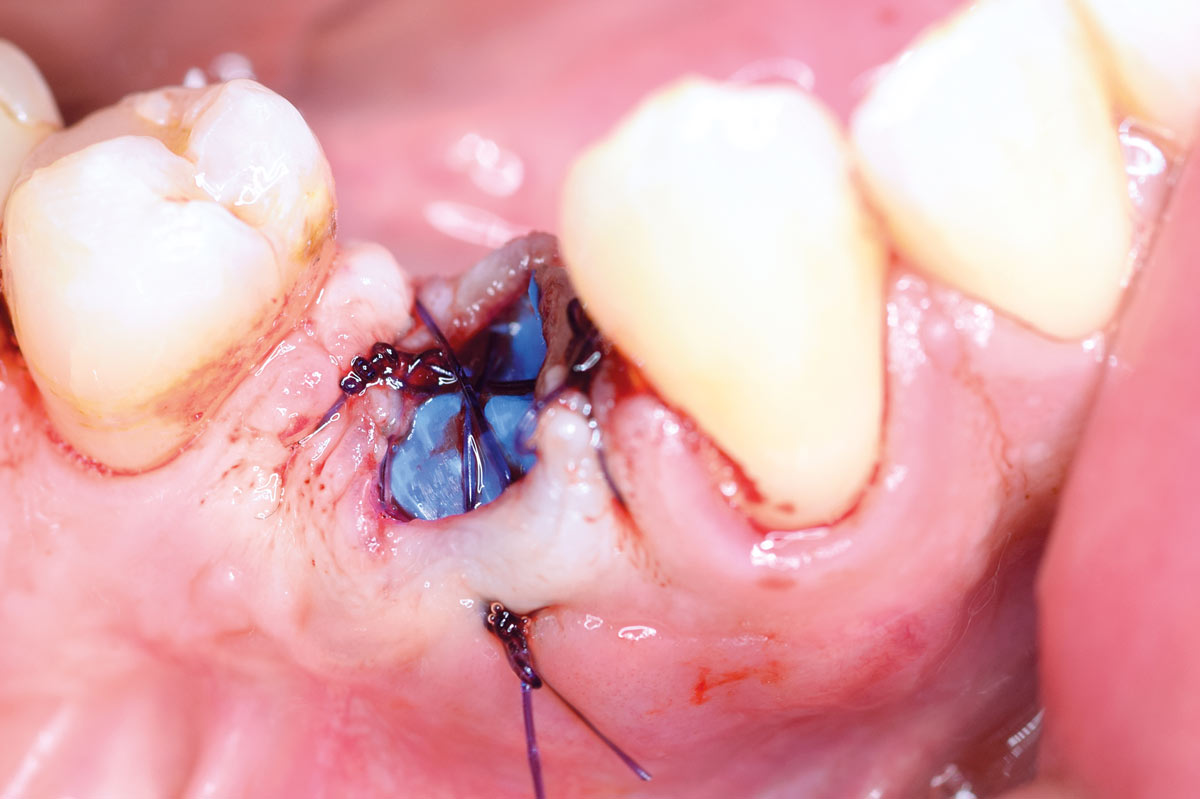

Full bone regeneration in extraction socket augmented with maxgraft® and Jason® membrane – Dr. C. Landsberg